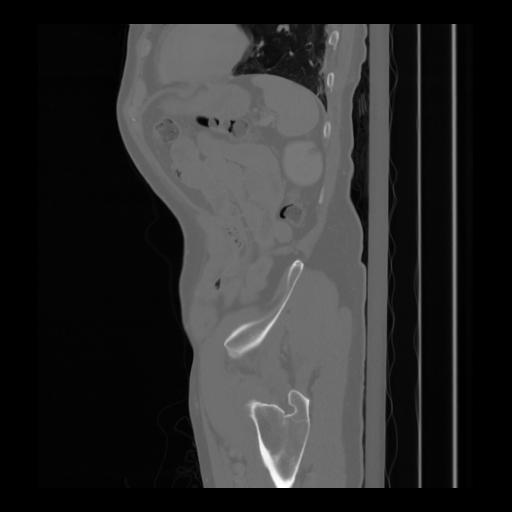

36 CUERPO,CE,Sagittal,3.000,CUERPO,Sagittal,